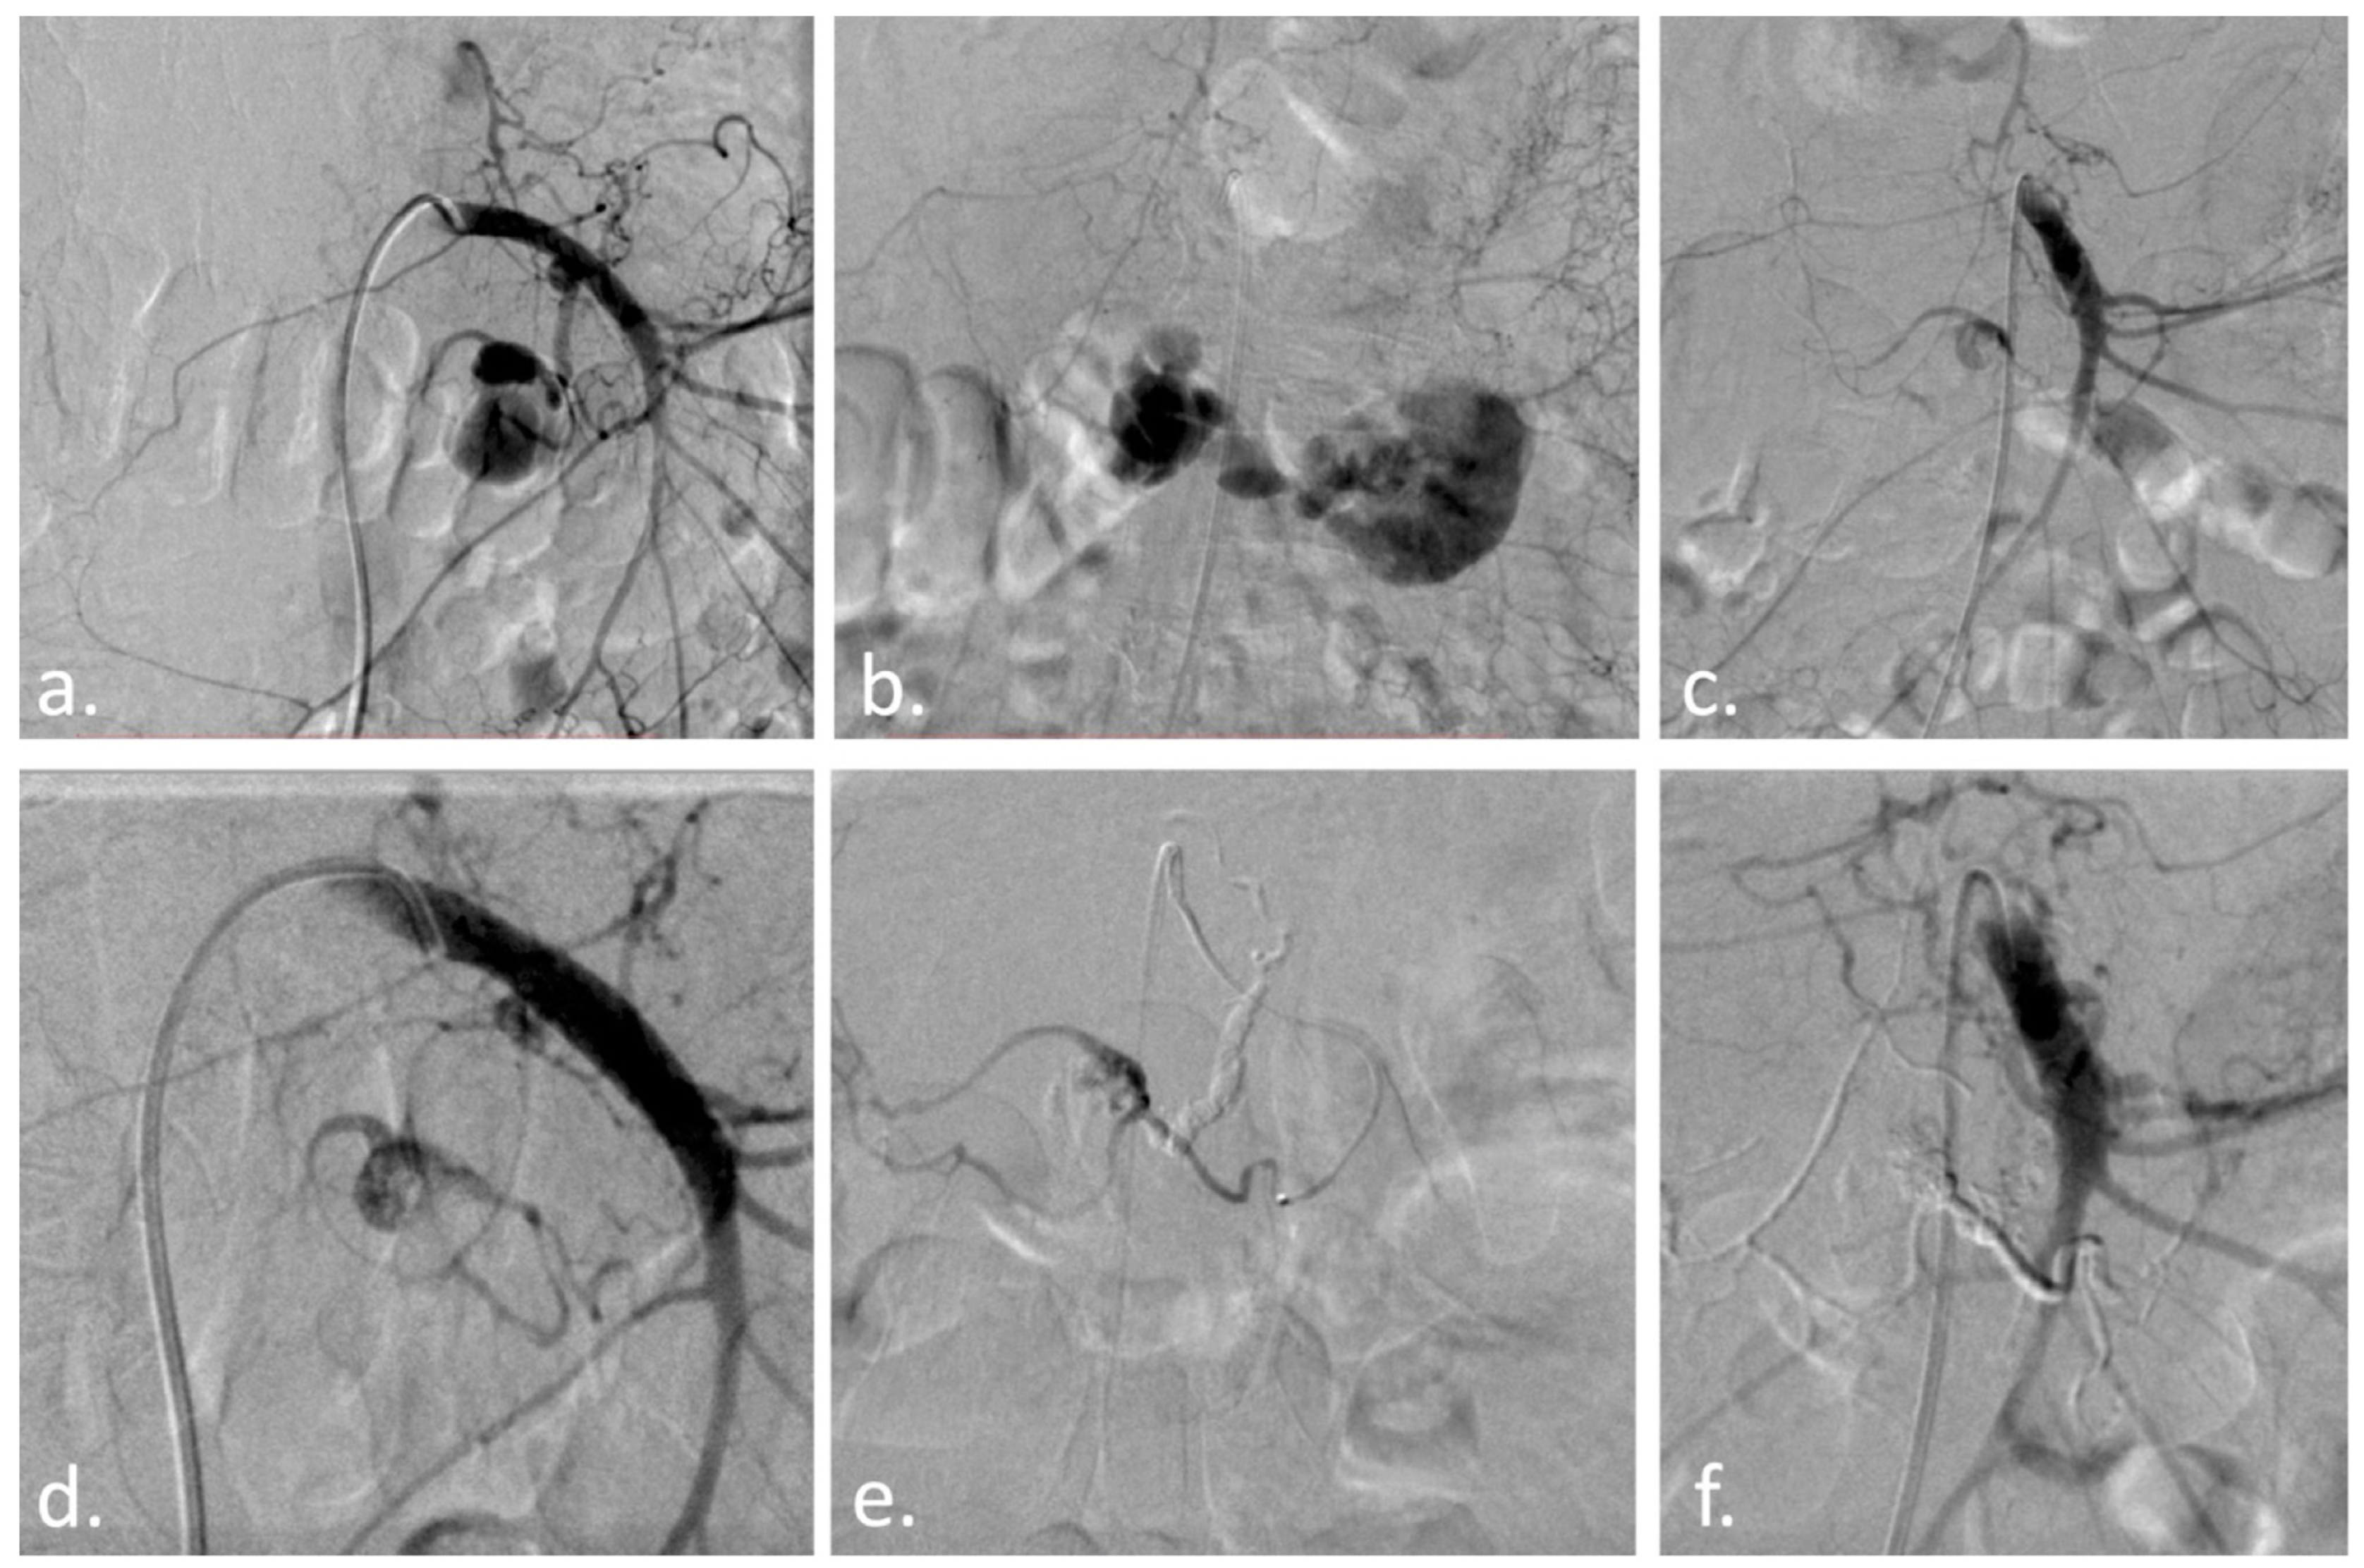

Figure 2. With the patient under conscious sedation, via a right common femoral artery approach, the superior mesenteric artery was catheterized with a 5F Cobra catheter and a Terumo 35 guidewire (Figure 2a). While injecting the contrast agent to obtain a better working projection, the pseudoaneurysm ruptured, and acute extravasation of the contrast agent was noted (Figure 2b). A Direxion microcatheter (Boston Scientific, Marlborough, MA, USA) with a 14 guidewire was selectively advanced in the inferior pancreaticoduodenal artery and another small pancreatic branch (Figure 2c–e), followed by injection of a mixture of 1 mL Glubran 2 (GEM, Viareggio, Italy) with 2 mL Lipiodol (Guerbet, Villepinte, France) until complete obliteration of the pseudoaneurysm was obtained (Figure 2f). The patient was hemodynamically stable at the end of the procedure and was discharged 6 days later in a good condition without any active bleeding signs. (a) Superior mesenteric artery contrast injection reveals an oval-shaped pseudoaneurysm; (b) Acute contrast extravasation during contrast injection; (c) Residual filling of the pseudoaneurysm through collaterals, despite IPD artery occlusion with glue; (d) Collateral branch responsible for residual filling; (e) Microcatheter in the inferior pancreaticoduodenal artery; (f) Complete obliteration of the pseudoaneurysm with the glue cast visible. Given the high morbidity and fatality rates associated with pancreaticoduodenal pseudoaneurysm rupture [23], immediate treatment is vital. Several recent studies in the literature demonstrate promising outcomes for endovascular embolization. Suzuki et al. [24] showed a series of seven patients embolized using micro-coils, with a 100% success rate and no long-term (28 months average, range 5–65 months) recurrence of symptoms or bleeding. Waguri et al. [23] also reported effective embolization of an anterior inferior pancreaticoduodenal artery pseudoaneurysm that perforated in the portal system. Furthermore, Krishna et al. [20] described a 60-year-old female patient who presented with melena and hematemesis caused by a rupture of the lower pancreaticoduodenal artery pseudoaneurysm at the level of the intestinal wall. Ren et al. [21] reported on their endovascular treatment of 159 patients with visceral artery aneurysms and pseudoaneurysms, with 96.9% of patients successfully treated and a 1.9% mortality rate at 30 days. Similar to our case, Mitrovic et al. [13,14,15] reported successful endovascular resolution of a posterior inferior pancreaticoduodenal artery pseudoaneurysm using the sandwich technique, in which the pseudoaneurysm inflow and outflow were embolized with coils. Jang et al. [16], on the other hand, embolized the pseudoaneurysm with an N-Butyl-Cyanoacrylate-lipiodol composition. Gurala et al. [17] also reported an effective embolization of a pseudoaneurysm from the gastro-duodenal artery, using coils. Inferior pancreaticoduodenal artery pseudoaneurysms may be diagnosed using ultrasound, CT, or visceral angiography with sensitivities of 50%, 67%, and 100%, respectively. An abdominal contrast-enhanced CT scan is usually sufficient for the appropriate identification of visceral pseudoaneurysms, but it should be confirmed through angiography and treated if necessary [13,14]. Treatments may involve direct thrombin injections, occlusive balloon catheters, surgical ligation, or percutaneous transcatheter embolization with coils or synthetic particles [9]. Vascular embolization with NBCA should proceed with extensive and careful evaluation of the vascular anatomy and close attention to technical details. NBCA is typically mixed with iodized oil (Lipiodol) for visualization under X-rays and to adjust the polymerization rate. Interventional radiologists should become more familiarized with these types of embolic agents, as they can be used as first-line treatment for various peripheral abnormalities [25]. Pseudoaneurysms of the visceral arteries are identified in up to 60% of cases at the level of the splenic artery, 25% of cases at the level of the renal arteries, and up to 20% of cases at the level of the hepatic artery. Additionally, with a considerably lower frequency of just under 5%, they are seen at the level of the celiac trunk, the mesenteric arteries, and in the smallest proportion at the level of the gastroduodenal and pancreaticoduodenal arteries [26,27,28,29,30,31,32,33,34,35,36,37,38,39,40,41,42]. Each patient with a visceral artery aneurysm should be treated individually and followed by a multidisciplinary team involving vascular and general surgeons, gastroenterologists, and radiologists for the best management choice. Endovascular therapy is the first option for these patients, based on our expertise and research published in the literature.